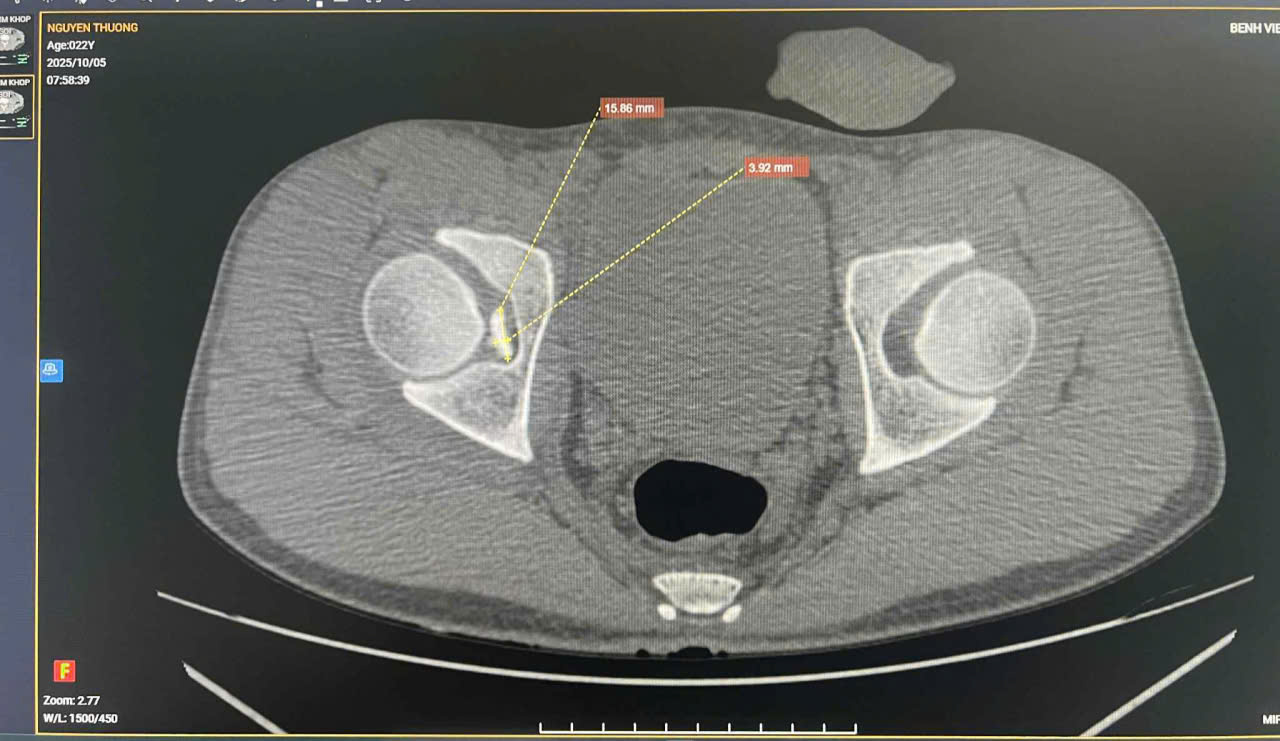

PHÁT HIỆN DỊ VẬT NỘI KHỚP HÁNG VÀ TỔN THƯƠNG MẠC GIỮ BÁNH CHÈ – ĐÙI TRONG CÙNG BÊN: VAI TRÒ PHỐI HỢP LÂM SÀNG VÀ CHẨN ĐOÁN HÌNH ẢNH 1. MỞ ĐẦU 📚Tổn thương phối hợp giữa dị vật nội khớp háng và mạc giữ bánh chè – đùi trong (Medial Patellofemoral Ligament –